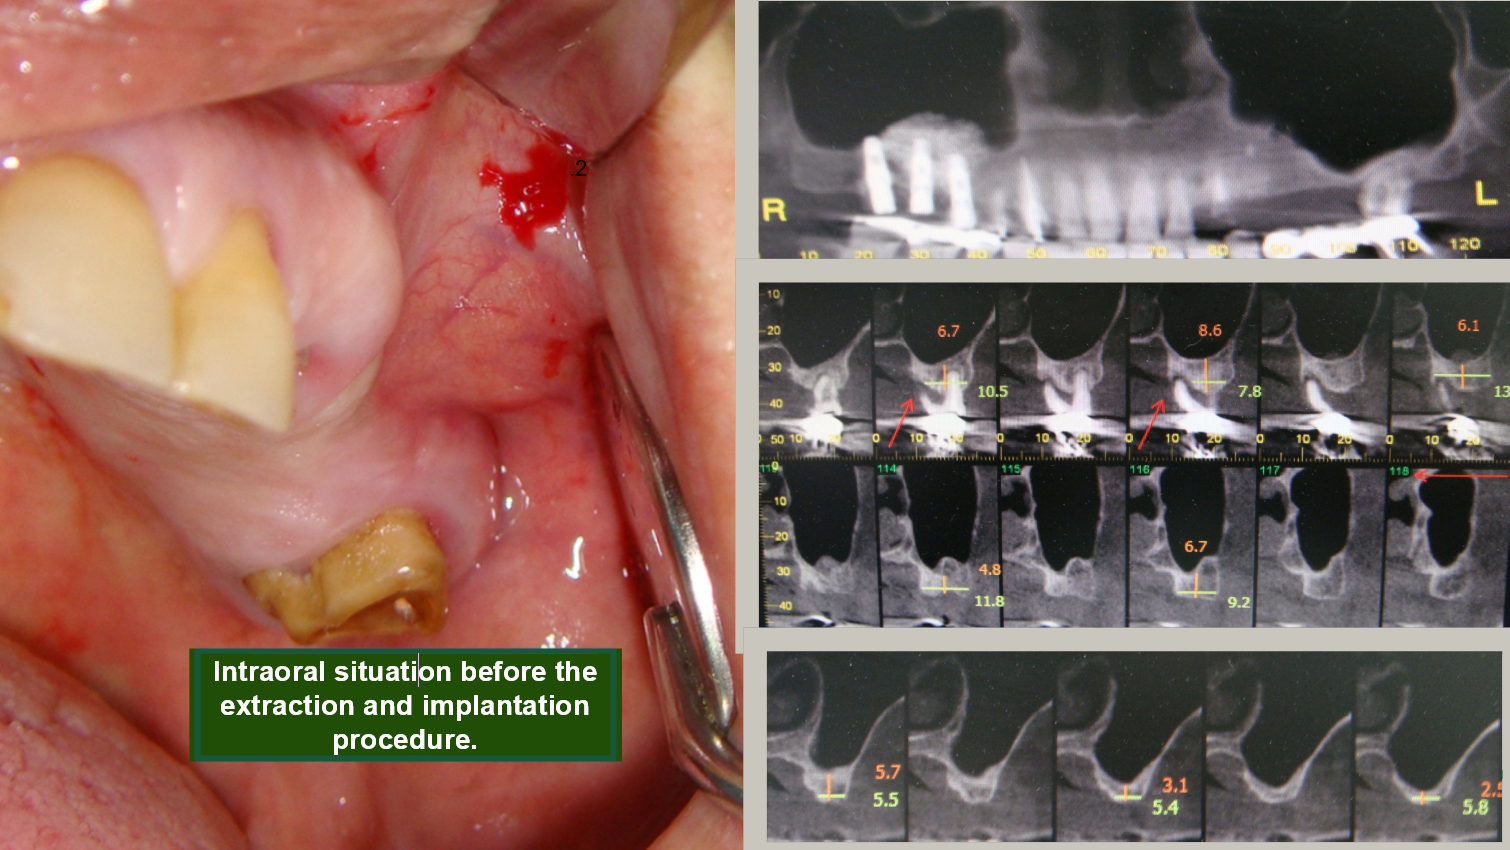

Teeth Extraction. Placing implants. Sinus lifting.